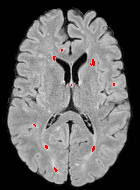

We observed that memberships predicted with an FC layer result in more false positives compared to a fully convolutional network. An example is shown in Fig. 2, where lesion memberships are generated from MPRAGE and FLAIR using the proposed model of convolutional pathways and a comparable model where the last convolutional pathway after concatenation (see Fig. 1) is replaced with a FC layer predicting voxel-wise memberships. The membership image generated with an FC layer, although being close to inside the lesions, has high values () in the left and right frontal cortex where the FLAIR image shows some artifacts. However, the membership obtained with the proposed method shows relatively low values near the frontal cortex.

With FC layer, voxel-wise predictions are performed for each voxel on a new image. Therefore the prediction time for the whole image comprising millions of voxels can take some time even on a GPU, as mentioned in Wachinger et al. (2017). In contrast, with fully convolutional prediction, lesion membership estimation of a mm3 MR volume of size takes only a couple of seconds. Note that although patches are used for training, the final trained model contains only convolution filters and does not depend in any way on the input patch size. Therefore during testing, the lesion membership of a whole 2D slice, irrespective of the slice size, is predicted at a time by applying convolutions on the whole slice. Without an FC layer, the images need not be decomposed into sub-regions, e.g., Kamnitsas et al. (2017). Consequently, there is no need to employ membership smoothing between sub-regions. In addition, since the training memberships, generated by Gaussian blurring of hard segmentations, are smooth, the resultant predicted memberships are also smooth (Fig. 2 last column).